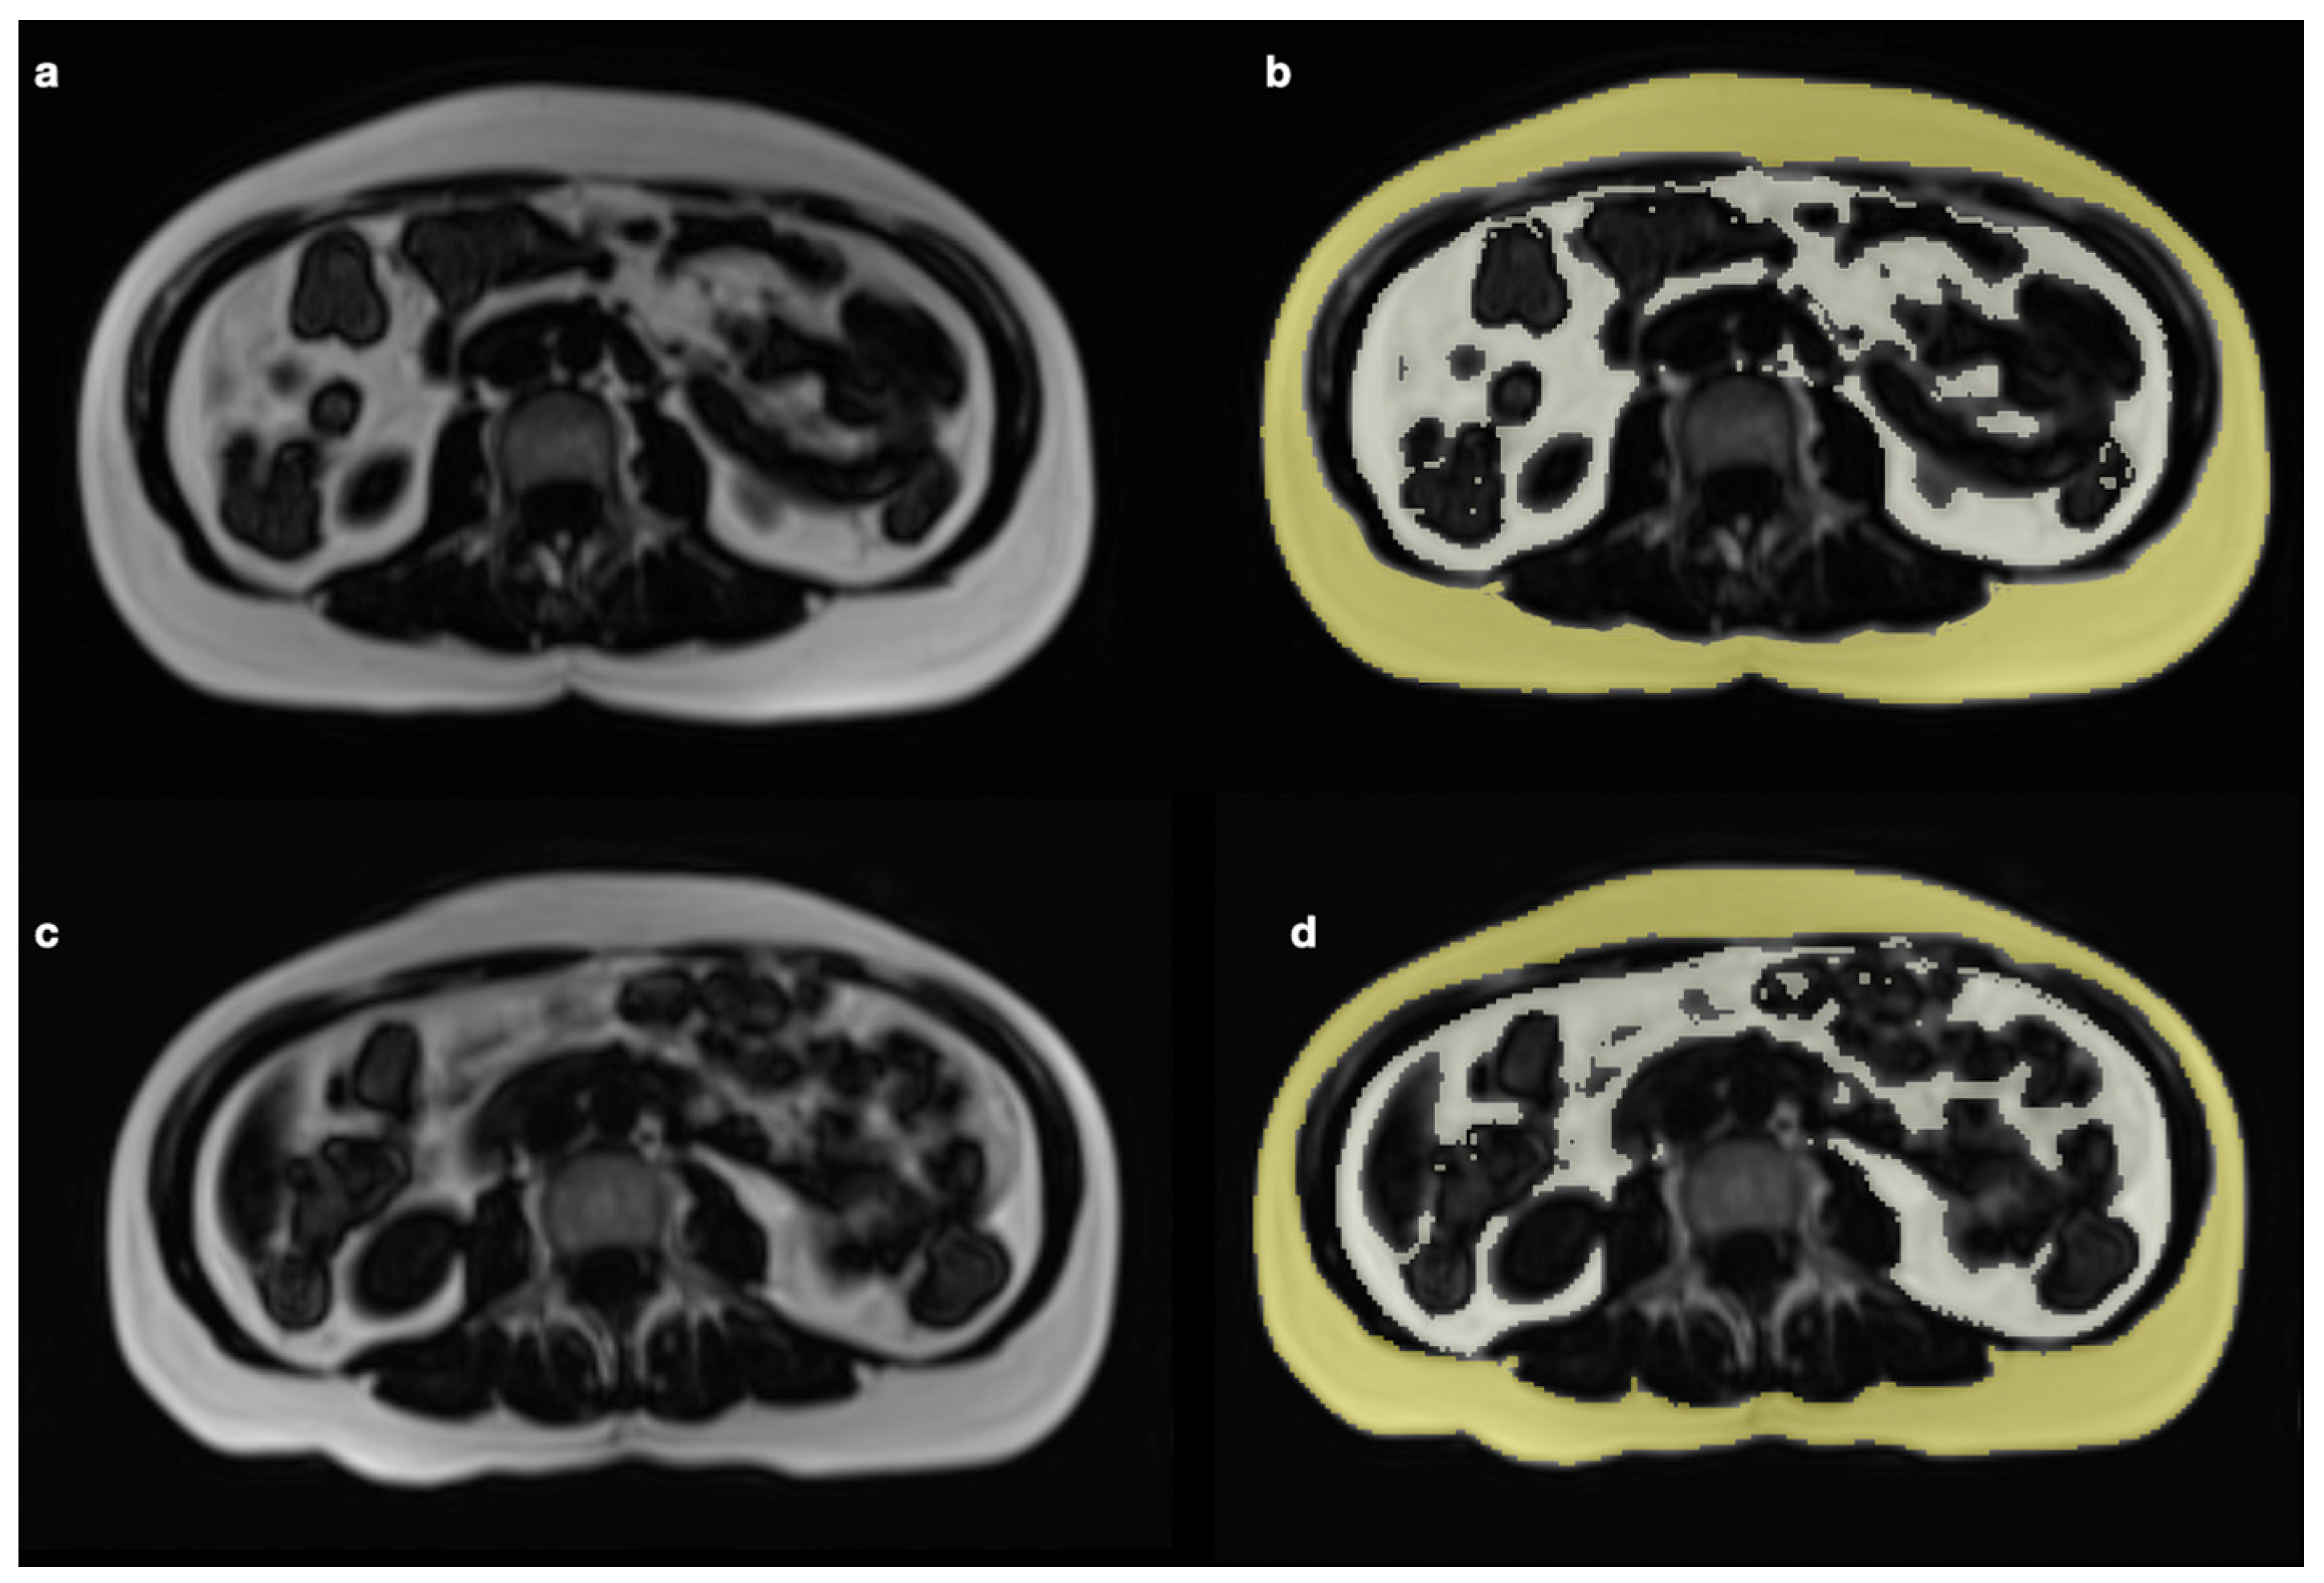

- Idoate, F.; Ibañez, J.; Gorostiaga, E.M.; García-Unciti, M.; Martínez-Labari, C.; Izquierdo, M. Weight-loss diet alone or combined with resistance training induces different regional visceral fat changes in obese women. Int. J. Obes. 2011, 35, 700–713. [Google Scholar] [CrossRef]